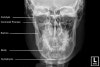

4) Adult Facial Bones - PA Caldwell